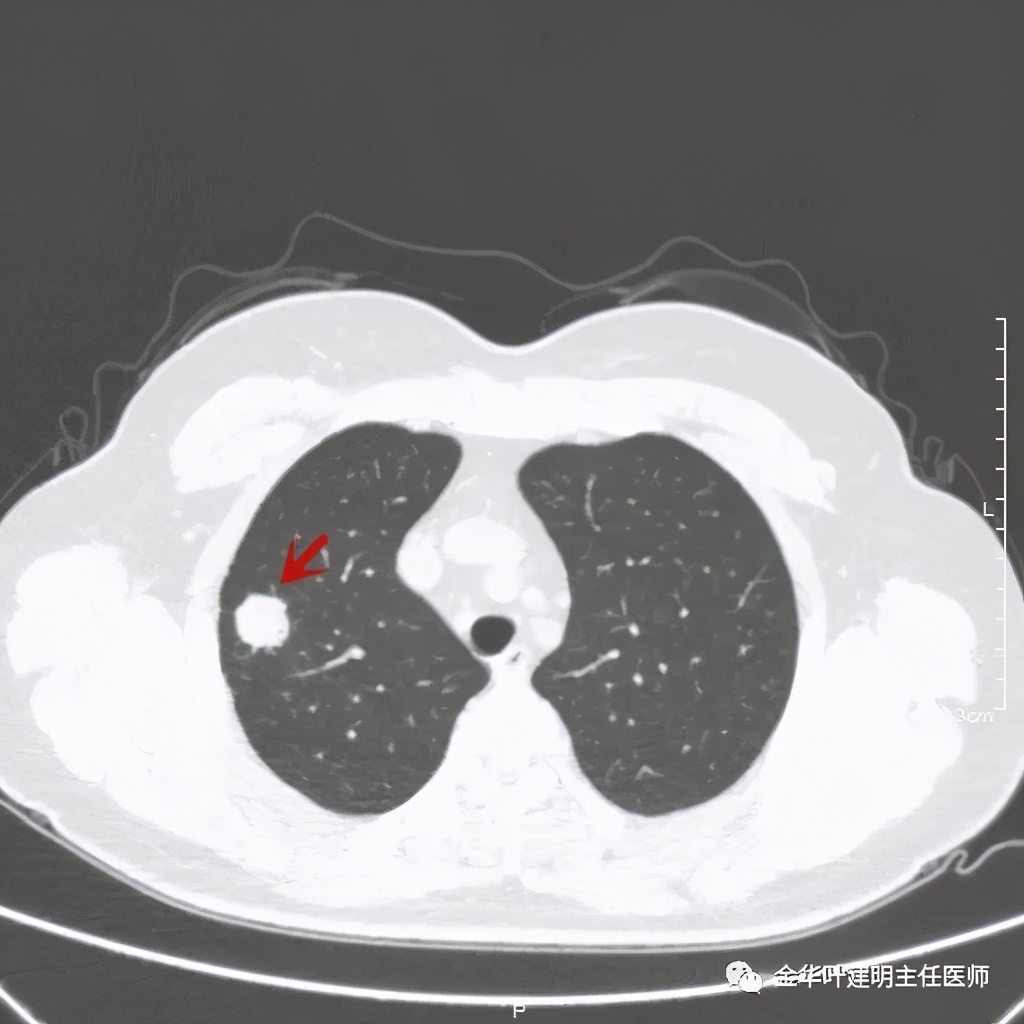

距主病灶一段距离的地方,也有小的实性微结节

总体感觉病灶较大,但边缘过于光滑,缺乏收缩力,没有毛刺征、分叶征、胸膜凹陷征;旁边却有多发微小实性或似磨玻璃结节,周围不清爽。让人感觉非肿瘤性质,炎性可能性大些,比如结核等。那么纵隔窗又是如何呢?我们选两个层面来看:

粉色箭头示病灶边缘光滑,没有毛刺,距胸膜近,但无牵拉凹陷。桔色箭头示病灶内有局部强化(血管?)

上图粉色箭头示病灶一侧非常靠边的地方居然有个小空泡:是结节内坏死形成的吗?这样大小的不符合呀,而且太靠边上了;是扩张的支气管吗?有可能,若病灶是肺癌,应该有破坏才比较符合,我们看它空泡比较光滑,没有堵塞或破坏。就是说,感觉与恶性是不太符合的。所以它应该是个良性的病灶!当然直径达2厘米的实性病灶,又这么靠外周部位,楔切非常简单,既可去除病灶,又可明确诊断,手术是可以考虑的。下面是术后病理结果: